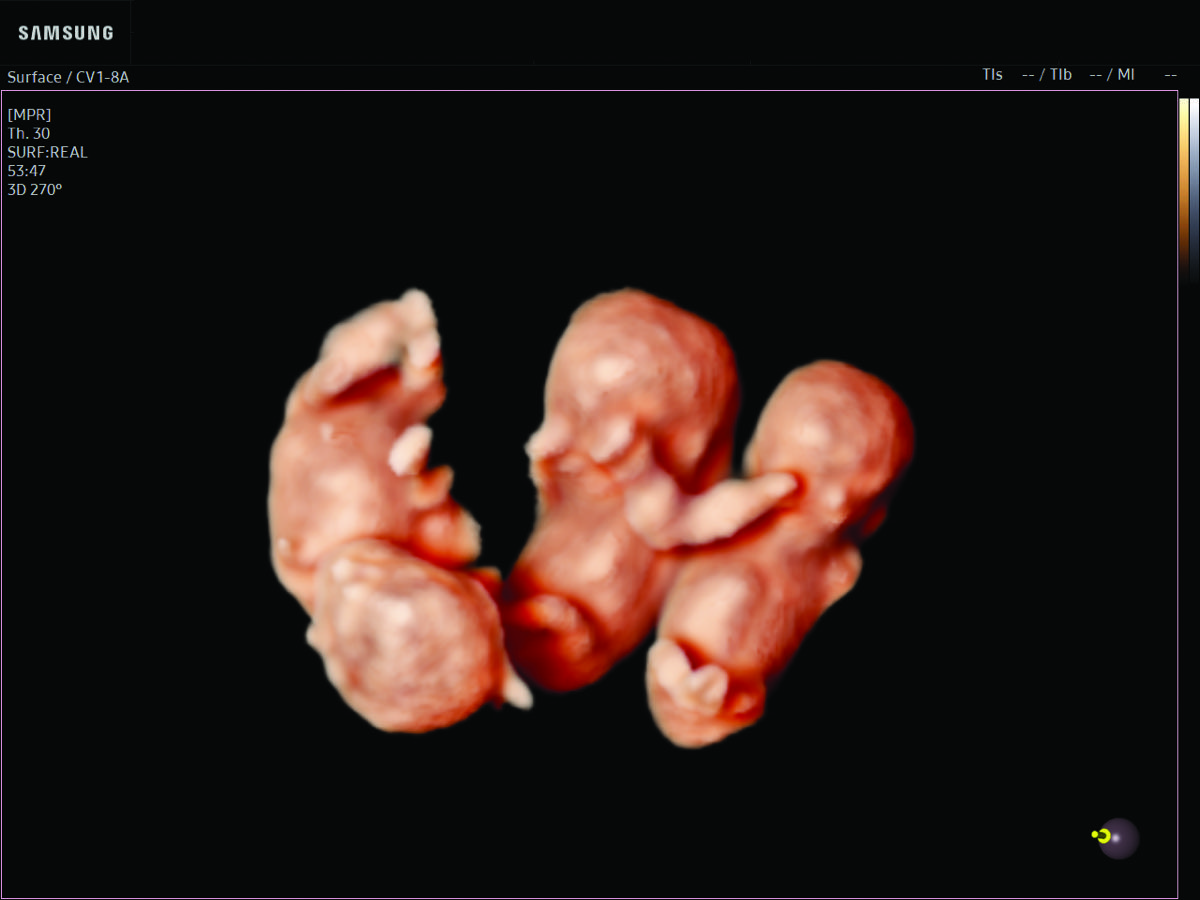

- Multiple births